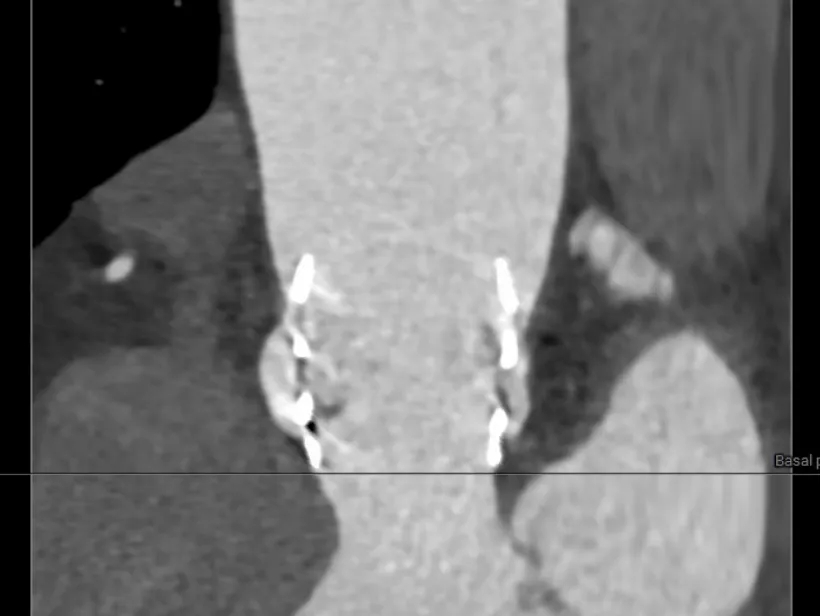

术后CT检查

术后CT可见瓣膜展开良好,CA对齐

长轴可见瓣膜位置理想